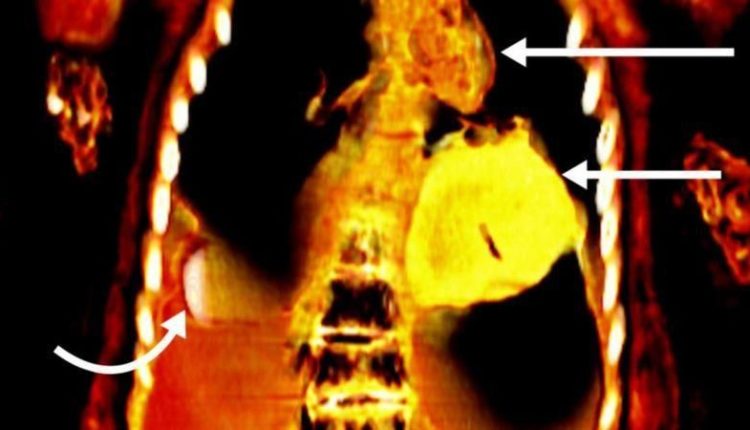

ஒரு நூற்றாண்டுக்கும் மேலாக இந்த உடல் வல்லுநர்களால் முழுமையாக ஆய்வு செய்யப்படாமல் இருந்த நிலையில், கெய்ரோ பல்கலைக்கழகத்தைச் சேர்ந்த சஹர் சலீம் தலைமையிலான குழு சிடி ஸ்கேனரை பயன்படுத்தி மம்மியை ஆய்வு செய்தபோது இந்த உண்மை தெரியவந்துள்ளது. இந்த உடலில் 21 வகையான 49 தாயத்துகள் இருந்தது இந்தச் சோதனையில் தெரியவந்துள்ளது. அதில், பெரும்பாலானவை தங்கத்தால் ஆனவை. இதன் காரணமாகவே இந்த மம்மிக்கு `தங்க பையன்` என்று பெயரிட்டதாக ஃப்ரென்டியர்ஸ் இன் மெடிசின்(Frontiers in Medicine) என்ற சஞ்சிகையில் வெளியான கட்டுரையில் சலீம் கூறியுள்ளார்.

கடந்த காலங்களில், மம்மிகளில் இருந்து கவச உறைகள் அகற்றப்பட்டு, ஆராய்ச்சி மற்றும் பொழுதுபோக்கு நோக்கங்களுக்காக அவை சிதைக்கப்பட்டதாக சலீம் கூறுகிறார். ஆனால், தற்போதுள்ள கம்ப்யூட்டட் டோமோகிராஃபி (computed tomography) நுட்பம், மம்மிகளை சேதப்படுத்தாமல் ஆய்வு செய்ய ஒரு சிறந்த கருவியாக மாறும் என்றும், இது பண்டைய கால மனிதர்களின் ஆரோக்கியம், நம்பிக்கைகள் மற்றும் திறன்கள் குறித்து கூடுதலாக ஆராயவும் உதவும் என்கிறார் சலீம். “கம்ப்யூட்டட் டோமோகிராஃபி கதிரியக்க துறையில் ஏற்பட்ட குறிப்பிடத்தக்க முன்னேற்றத்தைக் காட்டுகிறது. ஒரு படத்தைப் பயன்படுத்துவதற்குப் பதிலாக, இதன் மூலம் உடலின் சிறு பகுதிகளின் நூற்றுக்கணக்கான கணிப்புகளை ஒன்றிணைத்து முழுமையான முப்பரிமாண மாதிரியை உருவாக்க முடியும்” என்றும் சலீம் கூறுகிறார்.